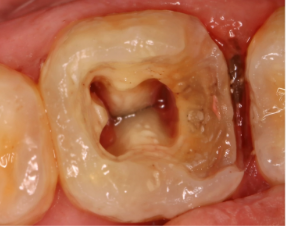

- ✔️ Painless Root Canal